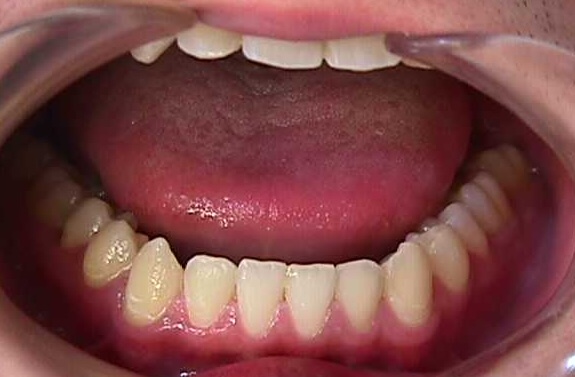

【矯正症例】左上2番3番逆転症例2

After

左上2番3番逆転症例

随分、前の症例で現在、写真しか残っておりません。

治療費や、治療期間を掲載できないことをご了承ください。

私の矯正歯科医の人生の中でも、特に思い出深い症例です。